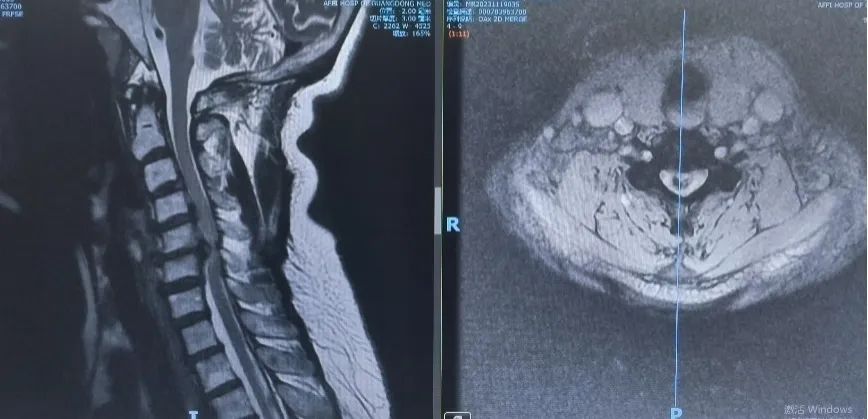

脊柱退变与畸形外科主任魏劲松教授为患者安排住院和详细检查。检查结果病情严重,在颈椎的第三到五节之间,有明显的已经钙化的病变椎间盘和韧带挤压神经,神经被挤得只剩下原来直径的四分之一,随时有彻底瘫痪的风险。这种情况下,只有将颈椎的部分椎体切除,才能解除神经压迫。然而这种手术不但风险巨大,而且要考虑将颈椎的椎体切除以后,如何替代原来的椎骨?通过与患者的仔细沟通,结合患者的病情,魏劲松教授决定采用3D打印的颈椎人工椎体置换手术来治疗患者的疾病。